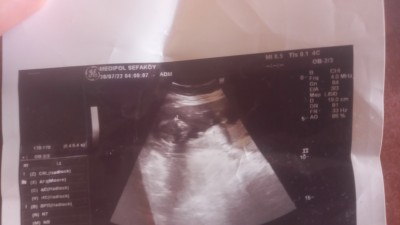

Kizlar 16 haftalık oldum ama hala cinsiyet belli degil diyor doktor kimi doktor kiz dedi kimi erkek dedi ama yanıltabilir belli degil diyorlar sizce kiz mi erkek mi ultrasondan anlayan var mı?

Gebelik haftası 16